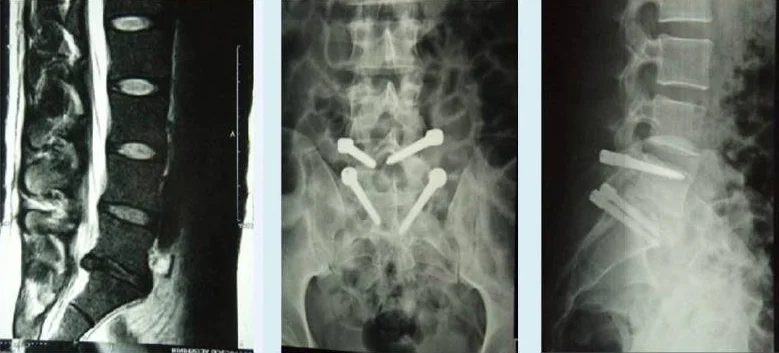

Paciente mostrando ressonância magnética com hérnia de disco lombar e radiografias pós-operatórias com sistema dinâmico